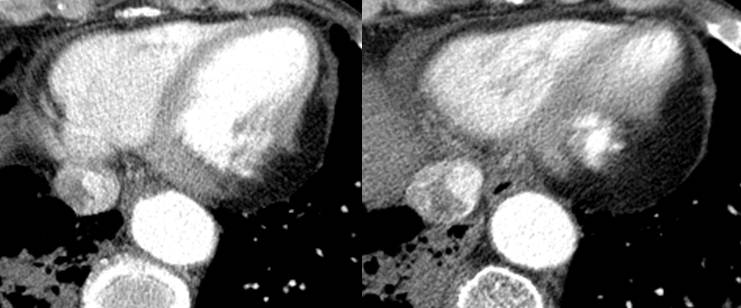

19 / M, Chief complaint: Recurrent episode of chest pain and cardiac enzyme elevation with normal coronary angiography, family history of sudden cardiac arrest

Jinwoo Son, Severance Hospital, Yonsei University College of Medicine